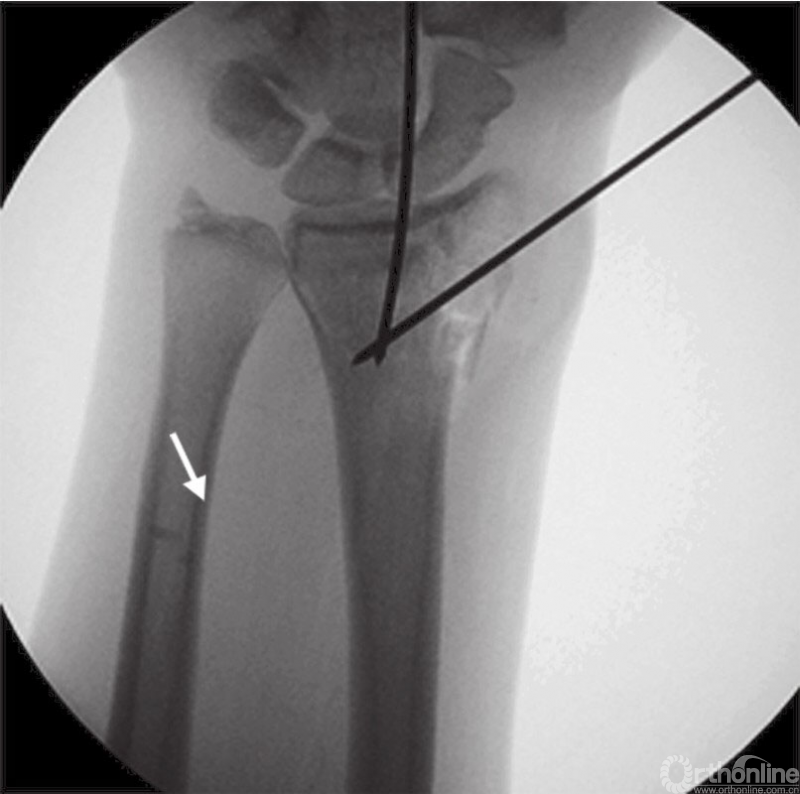

首先牵引复位骨折,1.4mm克氏针从桡骨茎突钻入临时固定骨折(图3),通过背侧置入克氏针撬拨技术复位背侧塌陷骨块,X线透视检查骨折复位情况。

图3 术中透视复位克氏针临时固定